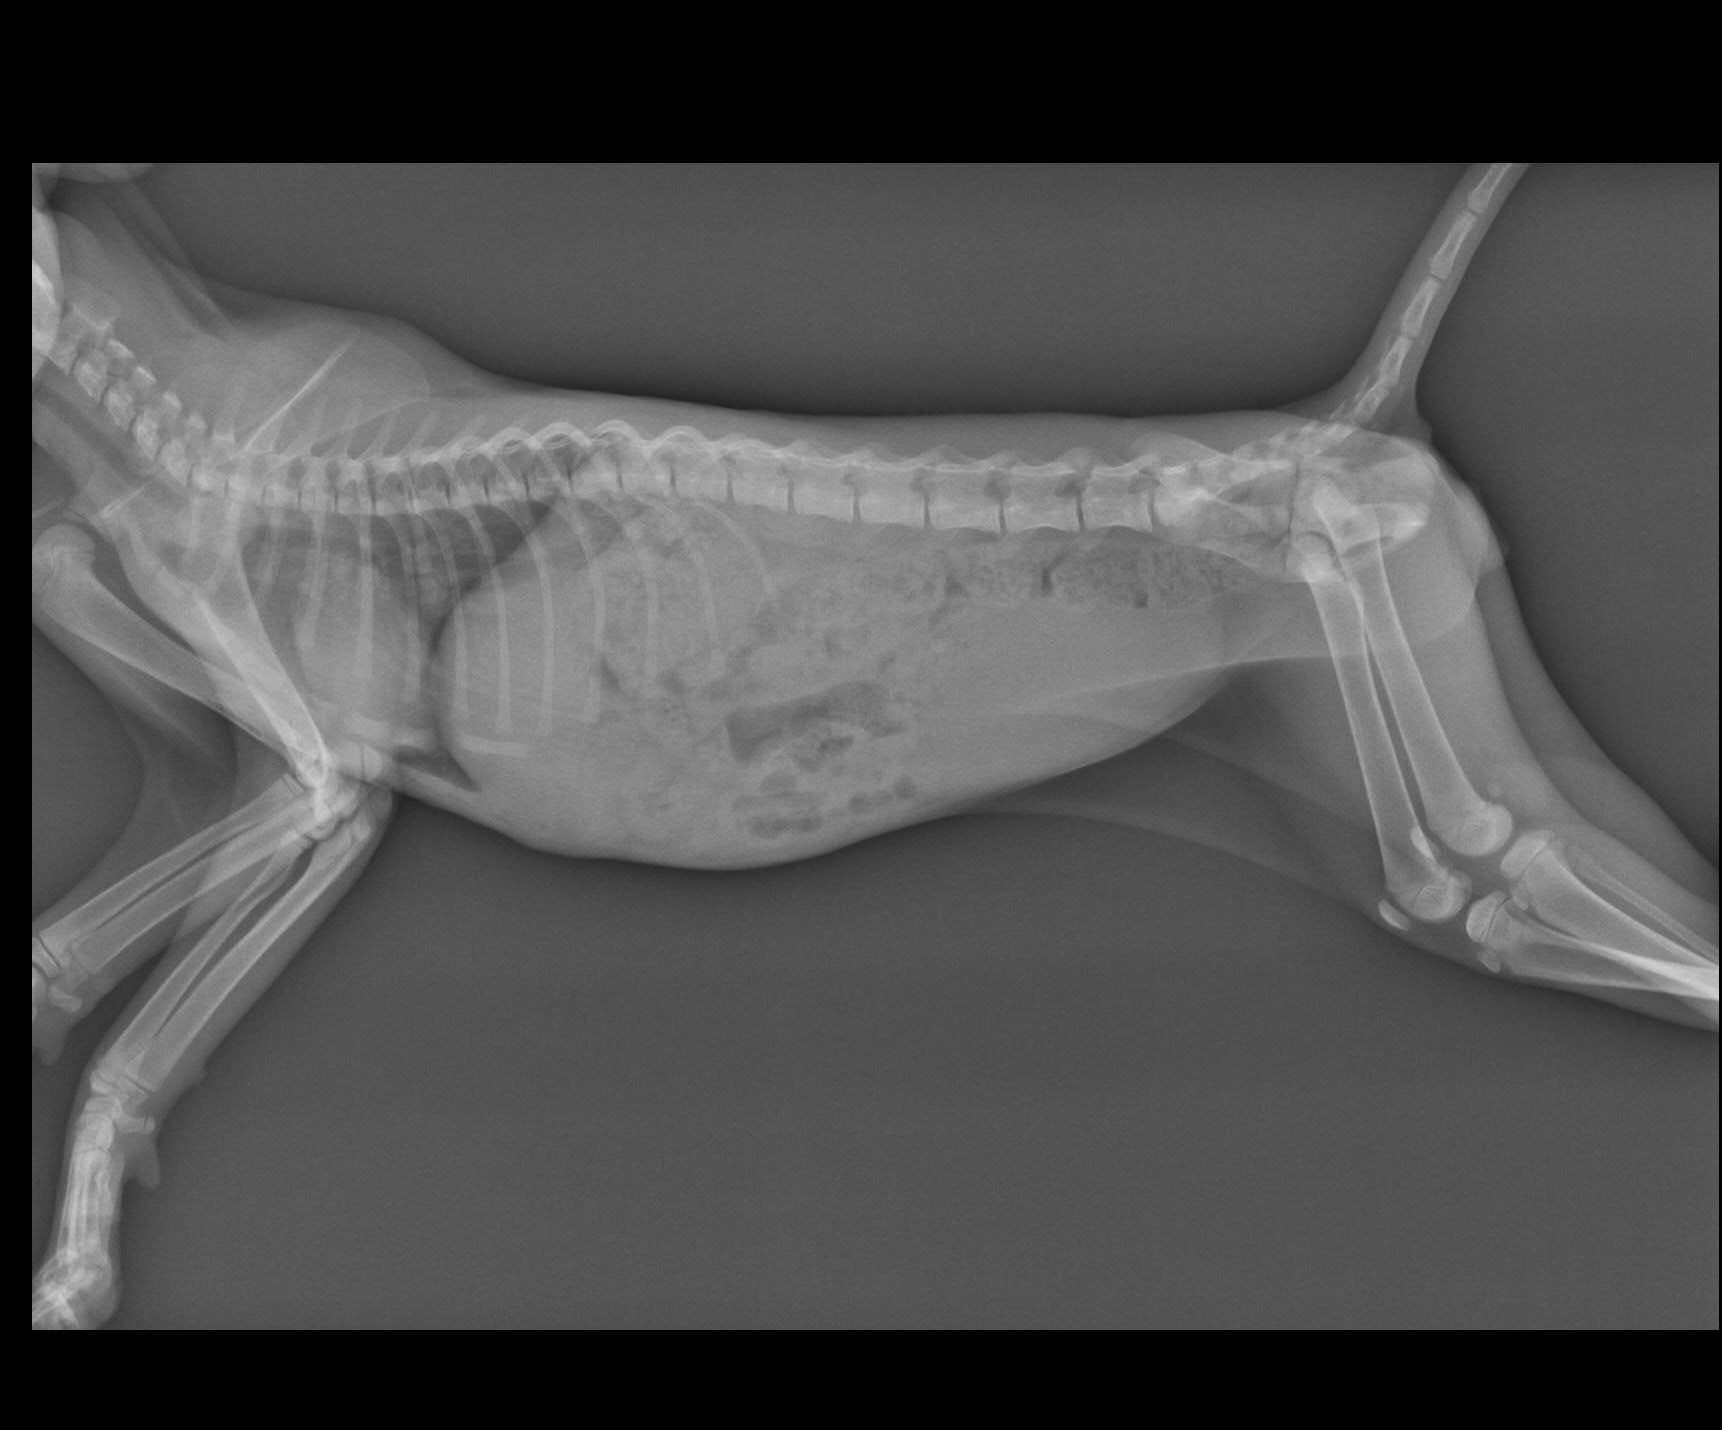

主題: 車禍黑貓 申請者姓名: 張菱予 花色: 申請日期: 2018-07-26 11:35:18 申請者部落格: 申請者臉書網址: http://www.facebook.com/clyanal 所在縣市/合作醫院: 高雄市/小新動物醫院 治療費用: 12150元 需求人數: 26人 已結案 (2024-06-01 13:09:58) 報名人員: 珊珊(已付款)、郁婷(已付款)、lin789 x14(已付款)、Fenny x10(已付款)、 候補人員: 動物病情說明: 晚上十點半在國道十號匝道口看到小黑趴在路中央不能動彈,高速公路上的車在小黑咫尺處疾駛而過,情況非常緊急,暫停路邊等待時機衝上前去把滿臉是血的他帶離路面!仔細查看發現小黑眼睛鼻子有出血狀況,四肢有反應但無力,僅能微微晃動,研判受到不小的撞擊!儘速送往小新動物醫院,醫生做初步觸診時小黑並無太大反應,雙眼緊閉,但是仍有意識、心跳,但有失溫狀況,趕緊給予保溫和輸液治療,先把生命跡象穩定下來再進行後續治療! 動物近況說明: 小黑到院後先穩定生命跡象,輸液治療並使用降腦壓藥物治療腦傷。接著照X光檢視是否有骨折,所幸小黑骨頭並未受到傷害。治療初期小黑並無法正常行動,僅能將頭微微抬起進食,但持續給藥輸液治療兩週後能正常行走,研判已無生命危險,故接出院自行中途照護。在此感謝各位捐款人,讓求生意志強烈的小黑能夠得到良好的醫療照顧!